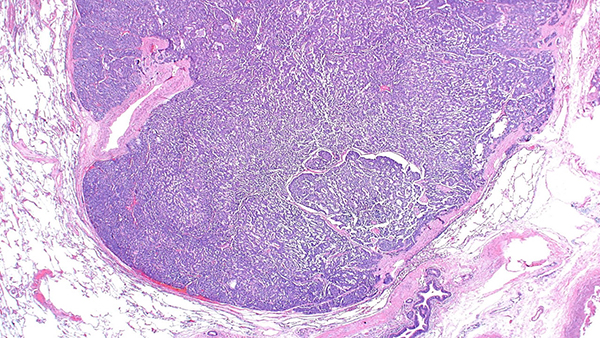

Clinical History: A 61-year-old woman presented with increasing cough and shortness of breath over a 3-month period. She was a never-smoker. Chest CT showed bilateral air-trapping and multiple subcentimeter nodules, the largest measuring 9 mm. She underwent diagnostic wedge resections from the right upper, middle and lower lobes (Figures 1-5, Figures 4 and 6: synaptophysin)

Histologic features include proliferation of pulmonary neuroendocrine cells (Kulchitsky-like cells) that may remain confined to the mucosa of small airways, spill into the lumen or extend across the basal lamina to form carcinoid tumorlets (Figure 2) or even carcinoid tumors (Figure 1). Carcinoid tumors and tumorlets are differentiated by a size cutoff of 5 mm. Carcinoid tumorlets embedded within fibrosis can destroy bronchioles, causing obliterative bronchiolitis. Figure 3 shows a small airway partially damaged by granulation tissue and neuroendocrine cells spilling into the lumen. Over time, the granulation tissue within the small airway may be replaced by scarring (Figure 5). These scarred airways can be identified by their location adjacent to a pulmonary artery (Figure 5). The neuroendocrine cells are cytologically bland and have a “salt-and-pepper” chromatin pattern. Immunostains for synaptophysin (Figures 4 and 6) and chromogranin are helpful in confirming the neuroendocrine nature of these lesions.